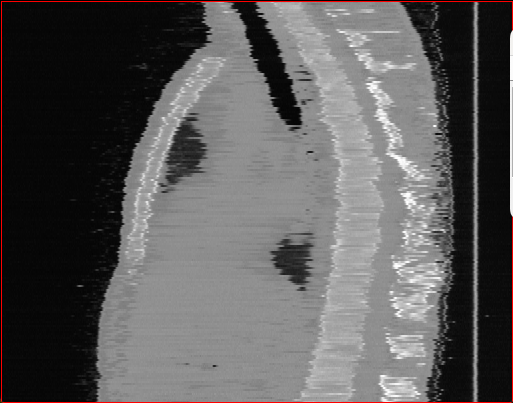

Figure 2: Qualitative comparison across axial (top row), sagittal (middle row), and coronal (bottom row) views. Columns correspond to different methods. MAISI-DDPM and MAISI-v2 in this figure are unconditional synthesis which do not use ControlNet or segmentation maps.

Qualitative Evaluation:

Figure 2 presents representative slices from the axial, sagittal, and coronal planes. GenerateCT (Hamamci et al. 2024) is a 2D model, so it lacks inter-slice consistency, leading to poor image quality in the sagittal and coronal views. MedSyn (Xu et al. 2024) produces noticeably blurry results with mosaic-like artifacts, such as region inside the red box. HA-GAN (Sun et al. 2022) generates visually sharp images but with mosaic-like artifacts, such as region inside the red box. Also, its voxel spacing is not available, which limits its applicability in real-world medical imaging tasks. Moreover, all three methods are restricted to synthesizing small anatomical regions. In contrast, both MAISI and MAISI-v2 are capable of generating high-quality 3D volumes that span larger body regions while preserving fine anatomical details and realistic structure.